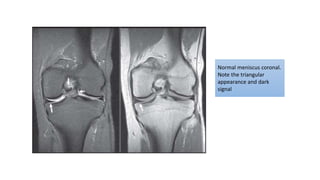

Normal meniscus coronal.

Note the triangular

appearance and dark

signal